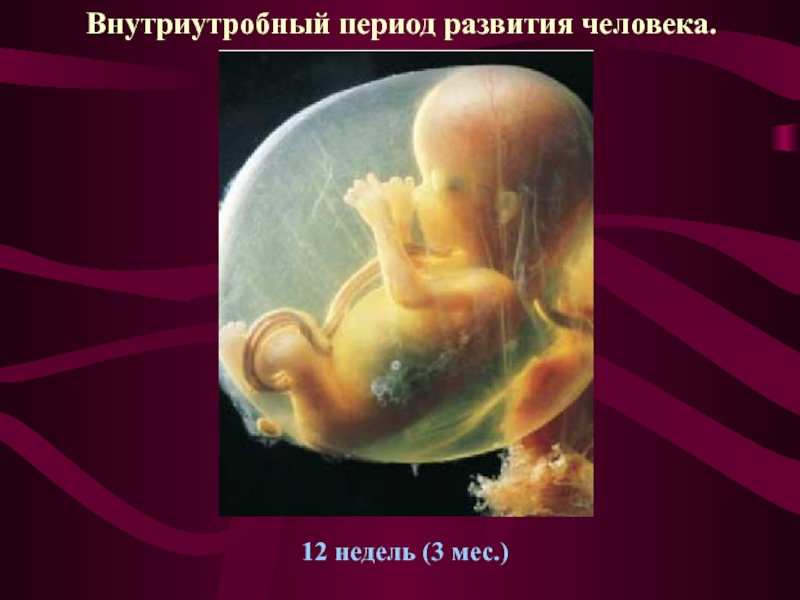

Развитие зародыша на 12 неделе: визуальный обзор